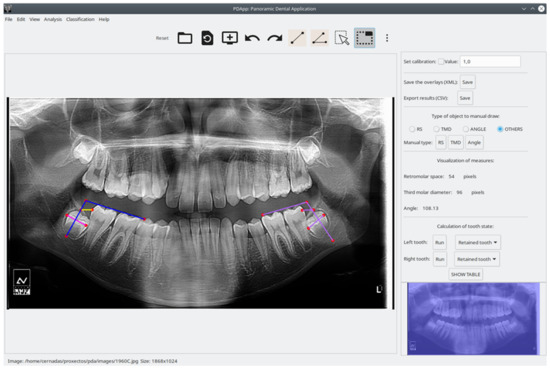

To evaluate PDApp based on operation in a real environment, the software was installed at the dental clinic of the Dentistry School of Medicine and Odontology of the University of Santiago de Compostela (Spain) in February 2021. Dental experts then used PDApp in their daily work to analyze images, which required that they manually draw the retromolar space and the third molar diameter and angle. PDApp then automatically classifies the third molars in radiological images as erupted or retained. Their operations using PDApp were logged into XML files for later statistical evaluation of the machine learning algorithm (SVM classifier) incorporated in the software. We used accuracy (rate of third molars correctly classified by the software) as a measure of the classifier performance. As mentioned, the classifier included in PDApp was initially trained using a dataset of 188 molars. Thereafter, PDApp was used to classify 539 third molars from 289 patients, and 97.96% of third molars were correctly classified. Figure 3 shows an example of correct classification of the third molar by PDApp as retained. Figure 4 shows a case of a third molar that is classified as erupted by PDApp.

Figure 3. Visual example showing two third molars analyzed, in which the PDApp prediction for both cases is correct as a retained tooth. The pink line represents third molar diameter, the yellow line represents retromolar space, and blue lines represent the angle of eruption. The lateral panel shows the measures for the left third molar (violet lines on the image represents the measurements realized).